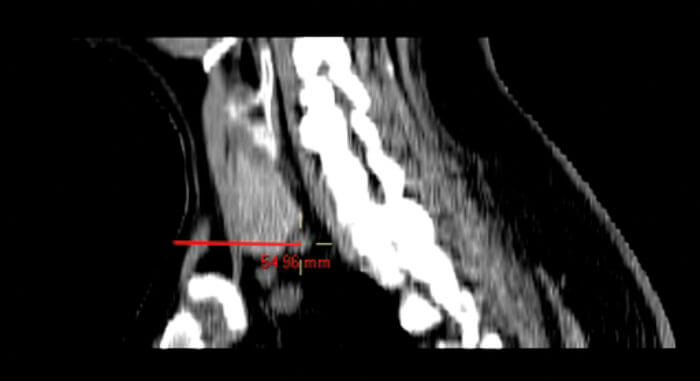

Using the PACS software, the corresponding CT images are viewed using multiplanar reconstruction (MPR). The PACS ruler is used to measure the following (see Figures 2-5).

Figure 5. Sagittal CT image showing distance from skin to PT gland (54.96mm), also confirms distance between inferior edge of thyroid gland to PT gland.